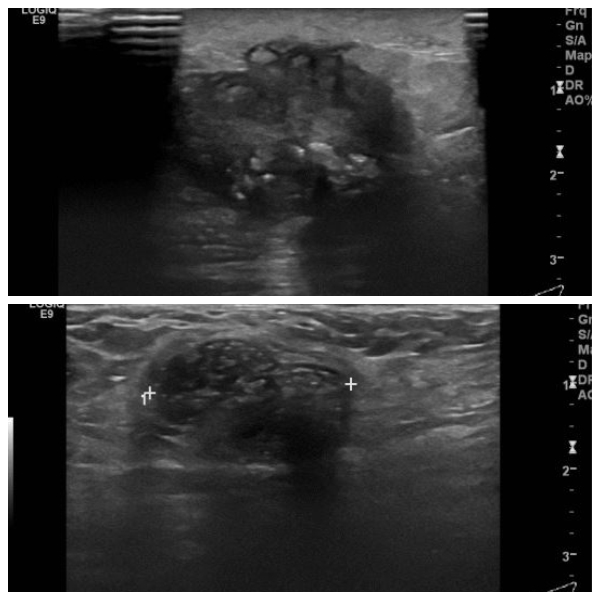

좌측 만져지는 멍우리로 내원하신 60대 여성분으로 좌측 12시 방향에 만져지는 혹

조직검사 시행하여 좌측 침윤성 유관암 진단 되었으며,  좌측 겨드랑이 림프절 비대

세포검사 시행하여 전이암의로 진단 되었습니다.